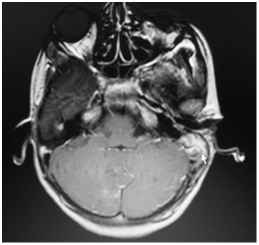

Although a CT scan is not required for patients with facial palsy, it can be useful in therapeutic planning. When cholesteatoma involves the Fallopian canal, it may also erode structures such as the labyrinth or tegmen. When petrous apicitis is suspected, a CT scan should be performed to make the diagnosis and to evaluate surrounding anatomy. CT scan will also aid in the diagnosis of intracranial complications that often accompany this condition.MRI accurately shows the site and extent of the apical abscess (Figure 4).

Figure 4 Axial T2 weighted MRI showing hyper intense region (arrow) in the left petrous apex.